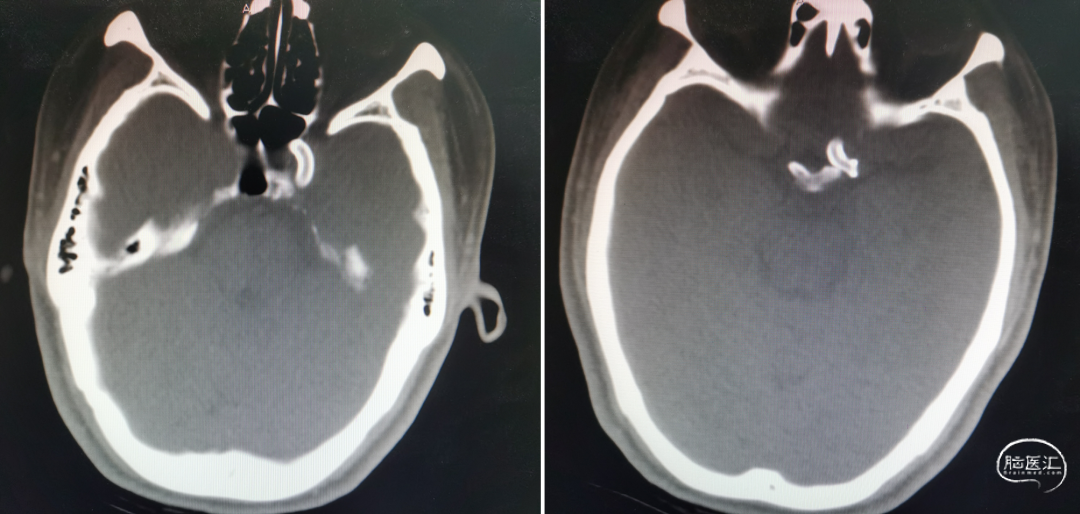

术后8个月复查CT(2022-12-25)